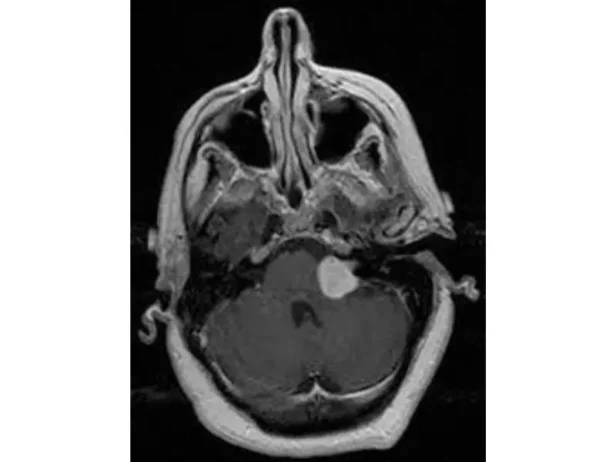

ورم العصب الثامن والسابع من الأورام الأكثر شيوعًا من أورام قاع الجمجمة ويمتاز بكونه حميدًا ولكنه عادة ما يسبب فقدان تدريجي للسمع وقد يؤثر على أعصاب مخية أخرى ولذا يتم التعامل مع هذه الأورام بدقة شديدة

تقييم هذه الأورام يتطلب الأشعات اللازمة كالرنين بالصبغة على قاع الجمجمة وتقييم حالة السمع والاتزان لدى المريض بعمل فحوصات مقياس السمع والاتزان وتقييم حركة عضلات الوجه وإحساسه وحركة البلع.

بعض هذه الأورام قد تستجيب للعلاج الاشعاعي أو تحتاج إلى المتابعة الطبية حال عدم وجود أي أعراض تضرر عصبي مصاحب لصغر حجم الورم ولكن أغلبية هذه الحالات تحتاج إلى جراحات أورام قاع الجمجمة عن طريق التدخل الميكروسكوبي للغرفة الخلفية لقاع الجمجمة و باستخدام التوصيل العصبي للأعصاب المخية.